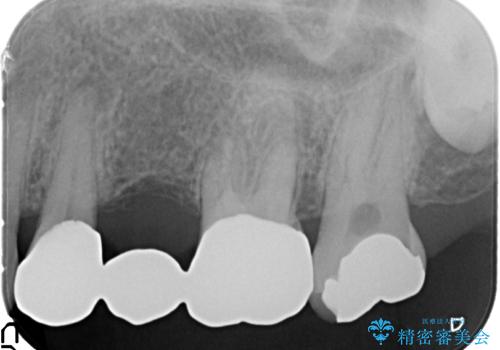

- 「老朽化し古くなった銀歯を白いものにやりかえたい。」と希望され来院されました。

銀歯の下には再発した虫歯やセメントの漏出が見られ、丁寧に除去したのちセラミックによるクラウン・ブリッジ補綴を行います。

適合や精度の悪い銀歯は、時間の経過とともに虫歯の再発リスクが高まります。